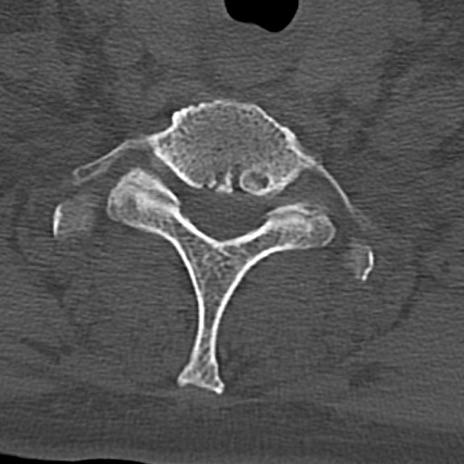

頚椎CT

横断像